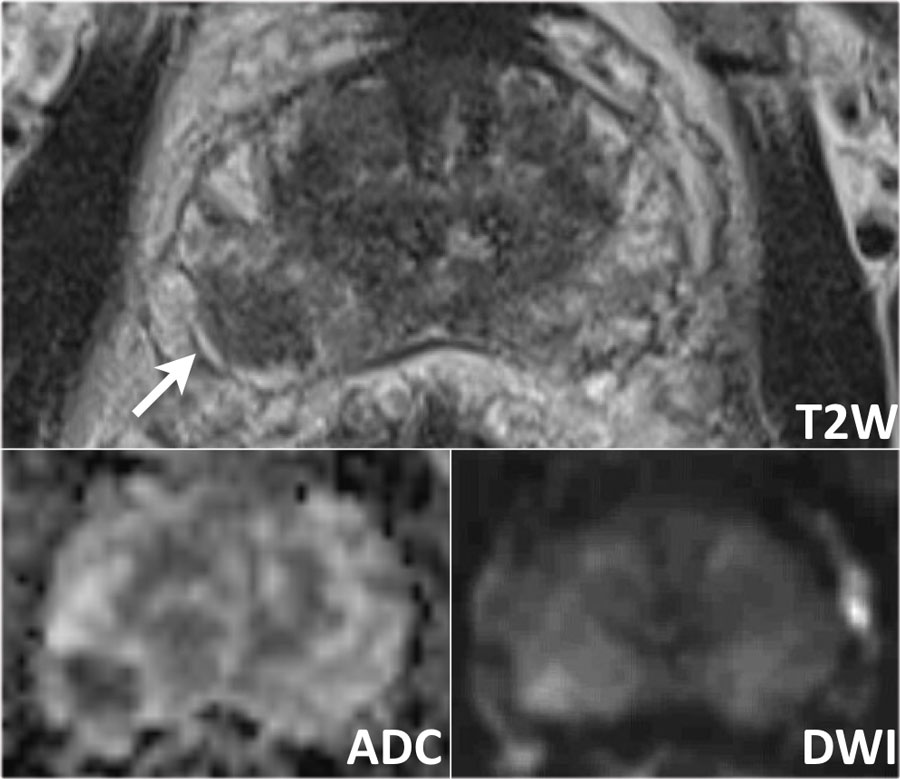

MRI to Diagnose Prostate Cancer – https://debuglies.com

MRI scan of prostate cancer – Santis | Private London prostate cancer …

[PDF] Local staging of prostate cancer with MRI. | Semantic Scholar

Prostate cancer, MRI scan – Stock Image – M865/0208 – Science Photo Library

Typical images show prostate cancer invading rectum. a. Pelvic MRI …

Extracapsular extension of prostate cancer on various sequences. (A …

Coloured MRI scan showing prostate cancer – Stock Image – M865/0142 …

The Radiology Assistant : Prostate Cancer – PI-RADS v2

Prostate Cancer Radiology : Multiparametric Mri For Prostate Cancer …

75 best images about MRI Technology on Pinterest

MRI: My Radiology Insight

The Radiology Assistant : Prostate Cancer – PI-RADS v2